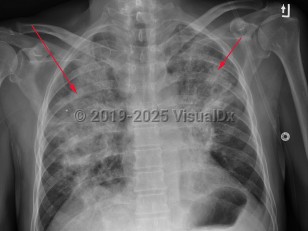

Herpes simplex virus pneumonia - Pulmonary

Herpes simplex pneumonia (HSP), or tracheobronchial infection, occurs when the respiratory tract is infected with the herpes simplex virus (HSV). HSP typically occurs in immunosuppressed patients such as those who are neutropenic from chemotherapy, immunosuppressed following organ transplantation, or are immunocompromised from HIV/AIDS or other immunodeficiency diseases. HSP has also been reported in patients who are not immunosuppressed. In most instances, infections were related to other risk factors such as smoke inhalation, recent major surgery, coexisting bacterial pneumonia, or airway injury from intubation. HSP is reported in all ages from infants and children to extreme old age.

Symptoms of HSP include dyspnea, fever, and nonproductive cough. Symptoms can be mild to severe; some patients can have a smoldering course with minimal fever. HSP is treatable with acyclovir but can be life threatening.